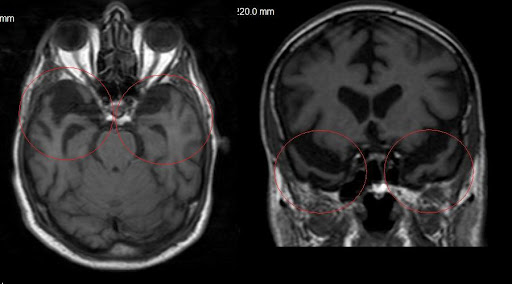

Retinadaki sinir lifi tabakasının kalınlığı daha önce bilişsel performansla ilişkilendirilmişti. Bu çalışmada da sinir lifleri, ganglion hücreleri ve iç pleksiform tabakası mercek altına alındı. Özellikle sinir lifi tabakası önemliydi çünkü görsel sinyalleri beyne taşıyan lifleri içeriyordu.

Ancak bu kez, araştırmacılar retinal mikrodamar sağlığının demans riskiyle daha güçlü bir ilişki gösterdiğini fark etti. Retinada bulunan küçük atardamarların (arteriyoller) daralması ve küçük toplardamarların (venüller) genişlemesi, demans riskinin artışıyla bağlantılı bulundu.